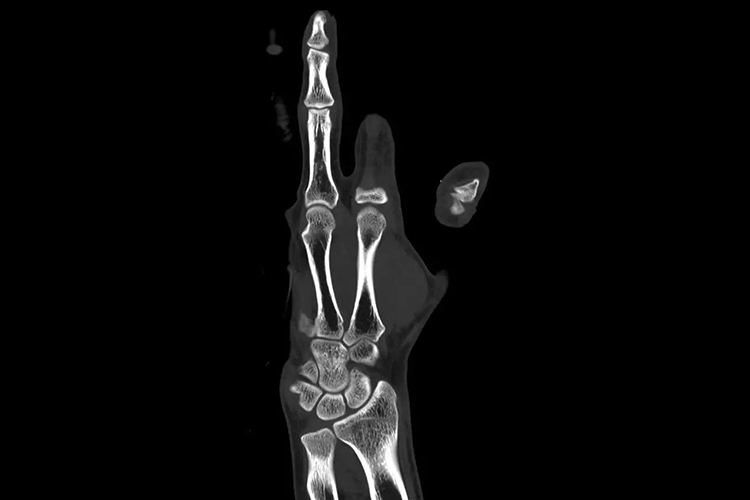

正常成人手骨在CT上可见其形态完好,位置正常,由腕骨、掌骨和指骨构成。腕骨共8块,包括手舟骨、月骨、三角骨和豌豆骨、大多角骨、小多角骨、头状骨和钩骨;掌骨共5块,包括第1-5掌骨;指骨共14块,拇指有2节指骨,其余各指均为3节,分别为近节、中节、远节指骨。手部CT通过CT后处理技术,可清晰看到各部分组织结构。